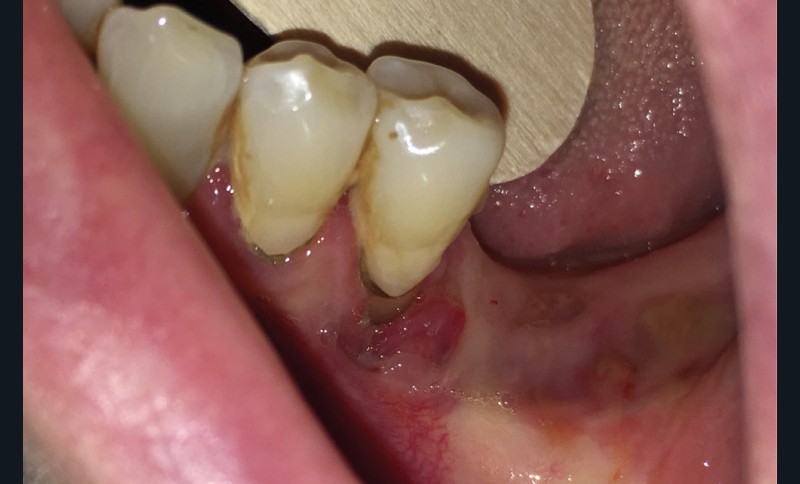

Dans le bilan avant mise en place du traitement, les recommandations, notamment de rhumatologie, indi-quent la réalisation d’un bilan dentaire et la mise en œuvre des soins nécessaires [1]. Cela a pour but d’identifier les foyers infectieux en présence et de les prendre en charge avant que le traitement ne débute, donc avant que le patient présente un risque infectieux accru (fig. 2).